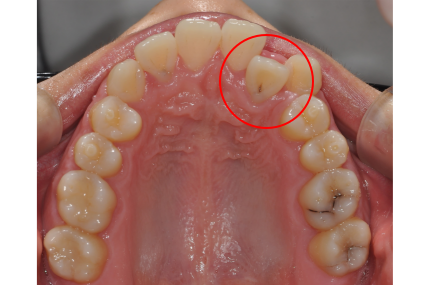

[치아교정] 앞니 교정, 앞니 틀어짐 – 부분교정을 통해 효율성 높이기

2025.12.03앞니가 살짝 틀어지거나 벌어진 것이 고민이신가요?

앞니만 살짝 비틀려 있거나 틀어진 경우